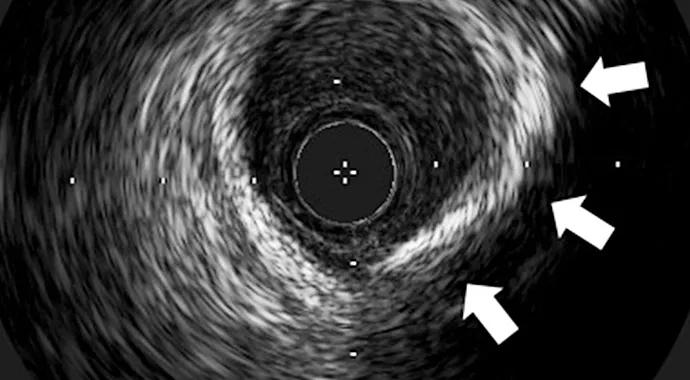

CT measurement of coronary calcium has traditionally been used to predict future CAD events. A total calcium score is derived from the extent of calcification detected in the coronary arteries, with higher scores representing more extensive CAD and thus a greater risk of CAD events. Calcium scoring via CT, however, has a much lower resolution compared with IVUS, which can elucidate subtle but significant changes in atheroma calcification (Figure) as well as plaque volume.

Figure. Intravascular ultrasound (IVUS) images representing cross-sections within the left anterior descending artery of (A) a noncalcified atheroma and (B) a calcified atheroma characterized by ultrasonographic shadowing in the region of the arrows.